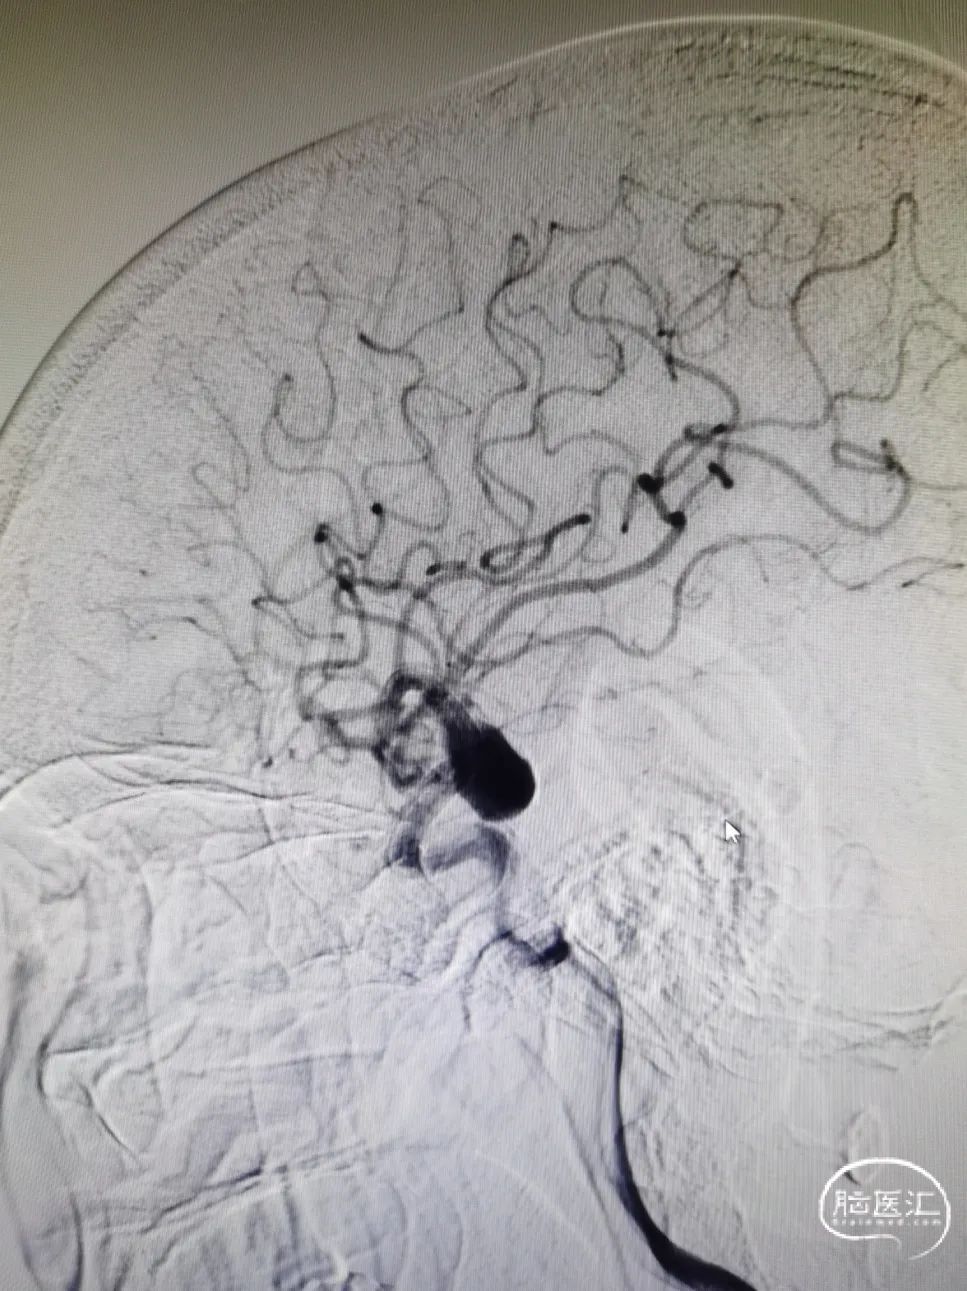

手术过程

图4右颈内动脉海绵窦段起始部类圆形瘤样扩张,最大约19mm╳14mm,瘤颈约14mm,瘤内射流明显,载瘤动脉远端5mm,近端4.5mm。

8F常规指引到右颈内动脉开口做近端支撑。Synchro 0.014 200微导丝及XT-27微导管引导CAT 5导管同轴越过右颈内动脉瘤至右大脑中动脉M1。由于动脉瘤颈较大,微导丝引导XT-27微导管,无法直接通过,采用瘤内成袢技术通过。选取Surpass Streamline 5mm╳30mm经CAT 5导管释放,并行微导丝及CAT 5导管按摩。

图5